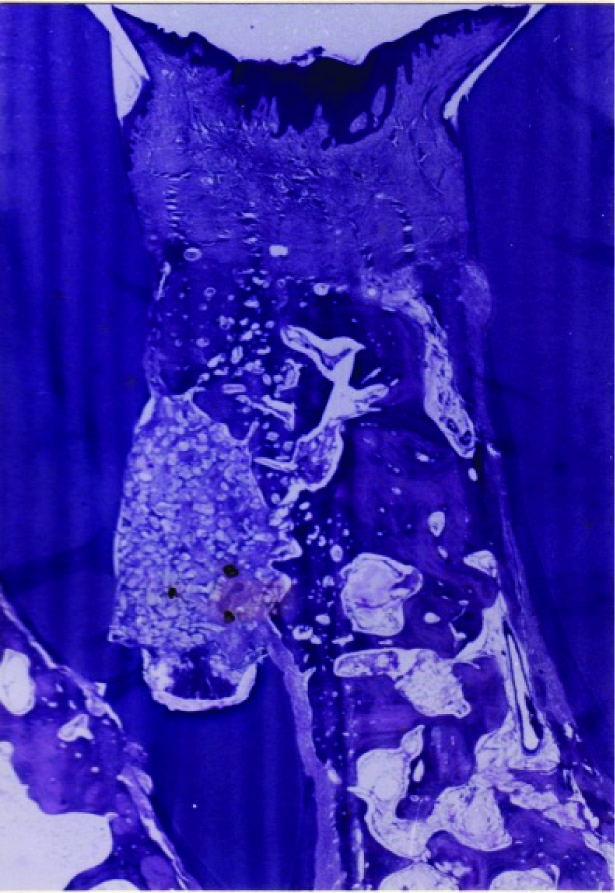

Histologic evaluation of undecalcified sections of Chitra Granules at 6 months: The cavity was completely filled by mature bone. Occasionally, Chitra granule particles were embedded in mature osteogenic tissue, whereas others were surrounded by fibrous connective tissue. Numerous chitra granules were present in the coronal portion of the cavity [Table/Fig-6]. Most of these granules were surrounded by fibrous connective tissue, though new bone appears to be in close contact with occasional Chitra granules.

Chitra Granules at 6 months: Photomicrograph showing A. Implant spaces B. New bone C. Marrow D. Osteocytes in non decalcified sections (Magnification 360X)